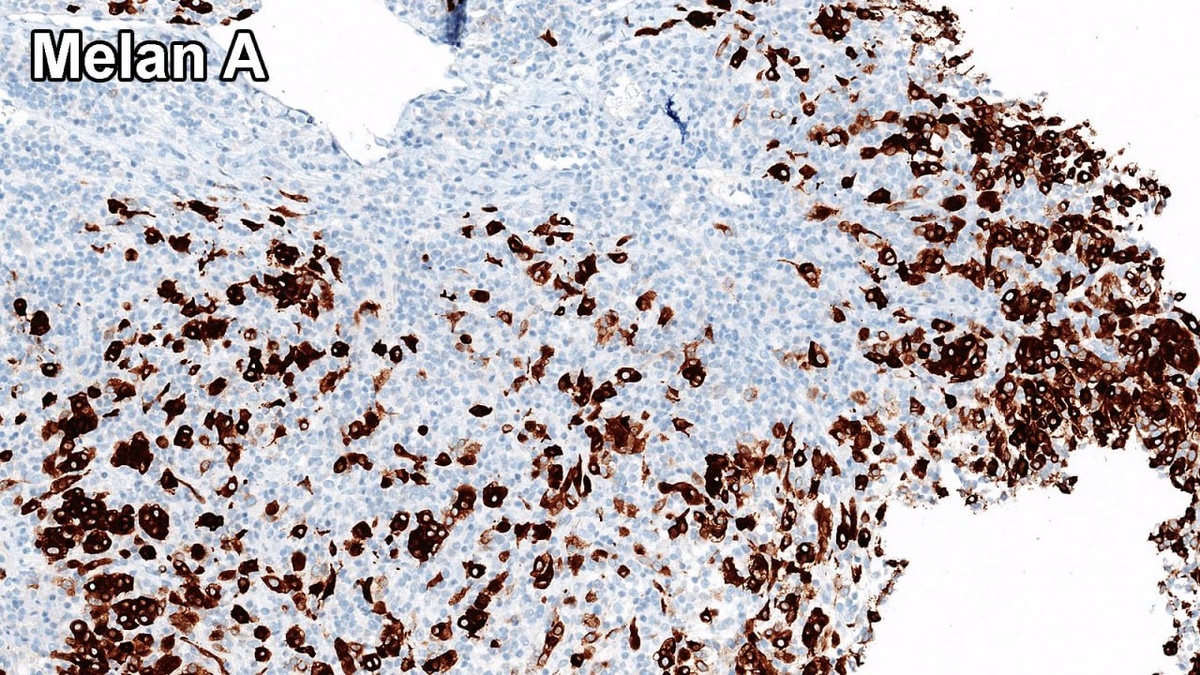

Метастатическая меланома в молочной железе — явление редкое, но вполне возможное.

Как известно, меланома заслуженно носит репутацию «великого имитатора». В данном случае она может приобретать плазмоцитоидную морфологию (как показано на фото) и имитировать картину инвазивной дольковой карциномы.